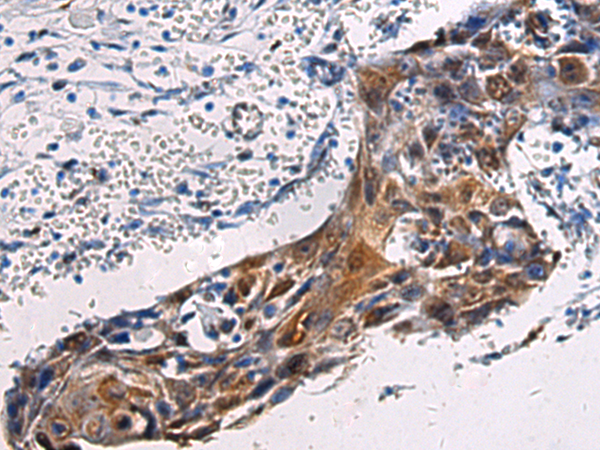

IHC 1/50-1/100 Human,Mouse,Rat